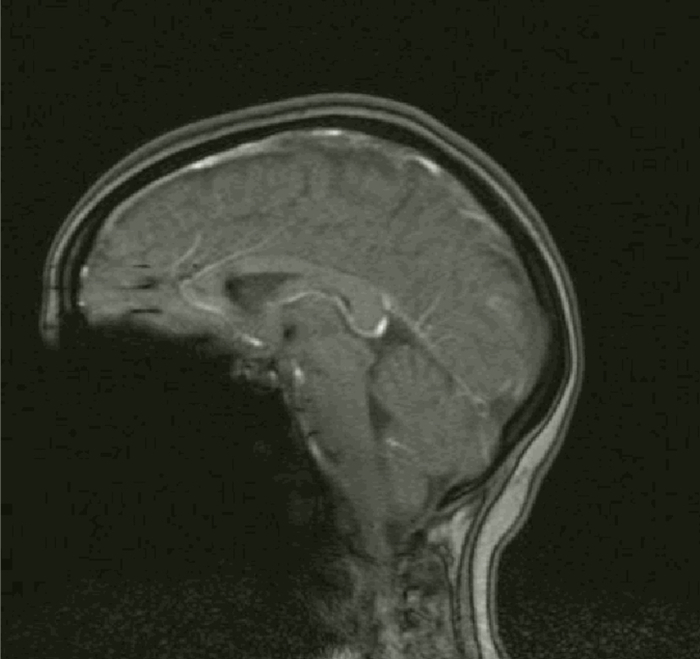

Ким Пик родился с отсутствием мозолистого тела, которое соединяет правое и левое полушария человеческого мозга. В детстве у настоящего человека дождя диагностировали множество отклонений в развитии. Врачи предупредили родителей, что он никогда не сможет ни читать, ни говорить, ни ходить. Они рекомендовали отправить ребенка в психиатрическую больницу. Несмотря на рекомендации, родители Кима решили воспитывать его дома. Благодаря усилиям своих родителей Ким получил возможность развивать свои удивительные таланты.